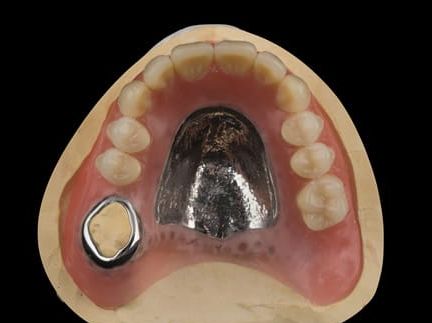

- UR7 - occlusal amalgam. 10- 20% alveolar bone loss. Healthy periodontium with reduced attachment level. No mobility.

- Cobalt chromium reinforced gasket denture - using a Molloplast B "O" ring to retain and stabilise the denture. This was my professional preference as this was the least invasive and simplest solution to this dental problem. Should the UR7 require removal in the future - an artificial tooth could be added - resulting in a complete denture. The patient would have adapted to the denture fully by this stage and have good neuromuscular control of the prosthesis.

Following consultation and second discussion appointment the patient chose to have option 2 namely, a window denture - maxillary cobalt chromium based partial denture. The clinical situation and treatment process is shown in detail below with photographs. The patient was successfully rehabilitated with this and her quality of life considerably improved. The clinical work was provided by Finlay and the technical work by Rowan.